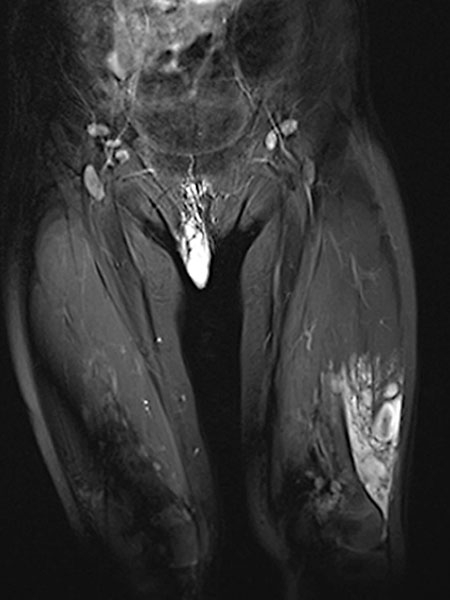

In coronal, T2-weighted, fat-suppressed MRI at 32 months of age, the characteristic strongly hyperintense (= white) signal of a slow-flow vascular malformation is found in the labial lesion. In addition, a similarly strong hyperintense signal in an intramuscular lesion is seen in the vastus lateralis muscle of the left thigh. Thus, a vascular malformation is very likely.

In the late phase of dynamic, high temporal resolution, contrast-enhanced MR angiography 135 seconds after i.v. contrast administration, there is slow, delayed contrast pooling in the lesion. Thus, an arteriovenous malformation with its rapid flow can be clearly excluded. Additional slow contrast pooling of the second lesion on the lateral distal left thigh.